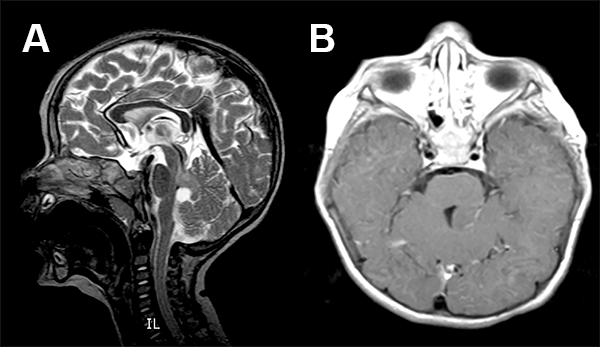

La RMN mostró una lesión tumoral en el hemisferio cerebelos derecho en intimo contacto con los pedúnculos cerebelos medio y superior derecho (fig. 6).

Figura 6: Caso 3. Imágenes prequirúrgicas.